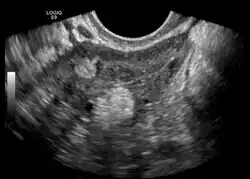

Die Dermoidzyste (früher auch Dermoidgeschwulst[1], im Volksmund auch fälschlich Zwilling[2] oder Zwillingsgewächs[3]) ist ein Hohlraum, der von Oberhautgewebe ausgekleidet ist. Die Dermoidzyste gehört zu den Teratomen.

Eine Dermoidzyste ist ein Keimzelltumor, ein reifes Teratom, das aus vollkommen verschiedenen Gewebearten besteht. Daher kann es innerhalb der Zyste zur Ausbildung von Gewebestrukturen wie Muskulatur, Knorpel, kleinen Knochen, Haaren und auch völlig ausgebildeten Zähnen kommen.

Im Gegensatz zu den Zysten, die während des weiblichen Regelzyklus entstehen und sich zumeist von selbst zurückbilden, ist die Dermoidzyste eine embryonale Fehlentwicklung.